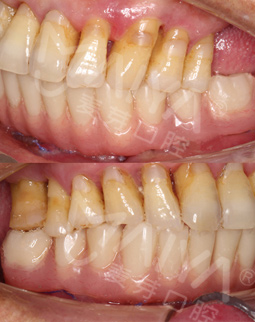

麦芽的博士专家团在看过我的片子后发现,我的牙齿由于长期对口腔疏于护理,牙周情况非常差,余牙有些松动,且牙槽骨萎缩严重,现存的骨量无法进行传统的种植牙手术,因此给我设计了“all-on-4”种牙技术的升级版本“all-on-5”,前期是要处理我的牙周问题,当天就给安排了洁牙,然后上药,等牙周恢复差不多就可以进行种植了!

我种牙后并没有什么不适,下牙的牙齿种好了,我又找麦芽的硕博专家把上牙的几颗牙齿也种了,绝对不能因为一颗坏牙再引发其他的口腔问题。临时牙冠佩戴没有任何不适,做了永久修复,而且麦芽的硕博专家还给我分析下牙和上牙的咬合关系,不能随便就戴牙冠,种的好是一方面,更重要的是咬合和使用功能。

这两年陆续去麦芽复诊,医生看完我的牙齿说维护的很好,需要坚持下去,不能因为种完牙就对它不管不顾,按时刷牙和用牙线清洁,据说我的种植牙维护的好可以用上好几十年,每天成本顶多才6毛钱,跟之前的假牙相比又美观,又舒服。